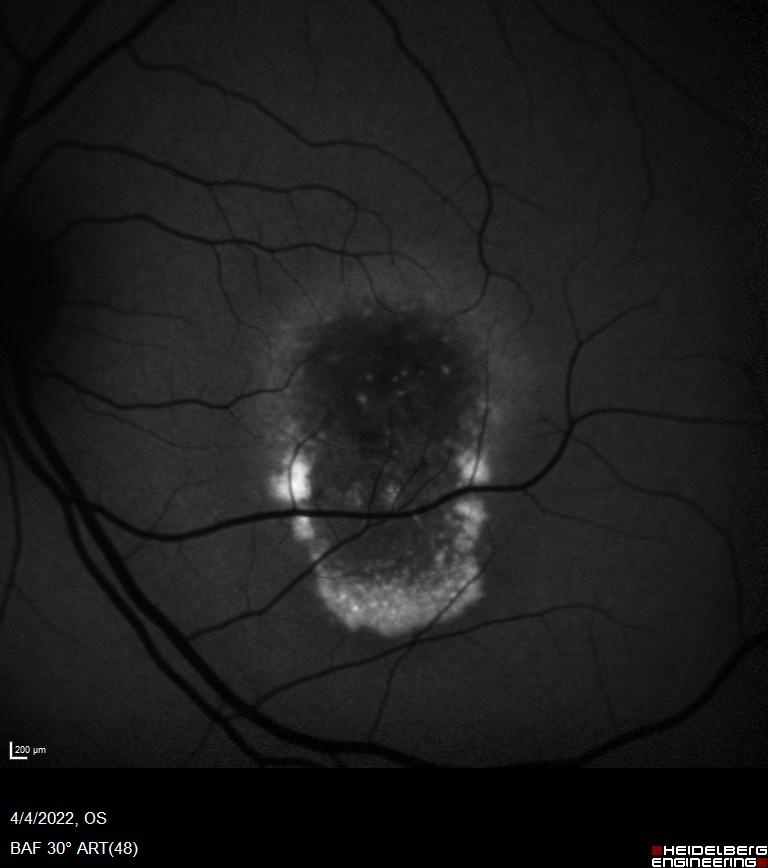

Η συγγενής φυλοσύνδετη ρετινόσχιση είναι μια κληρονομούμενη δυστροφία του αμφιβληστροειδή η οποία οφείλεται σε μεταλλάξεις του γονιδίου RS1. Εμφανίζεται με μείωση της κεντρικής όρασης σε νεαρούς άρρενες. Ο ηλεκτροφυσιολογικός έλεγχος (Ηλεκτροαμφιβληστροειδογράφημα) είναι πολύτιμος για τη διάγνωση της νόσου μιας και έχει χαρακτηριστικά ευρήματα στις καταγραφές ενώ ο γενετικός έλεγχος ταυτοποιεί τη διάγνωση.